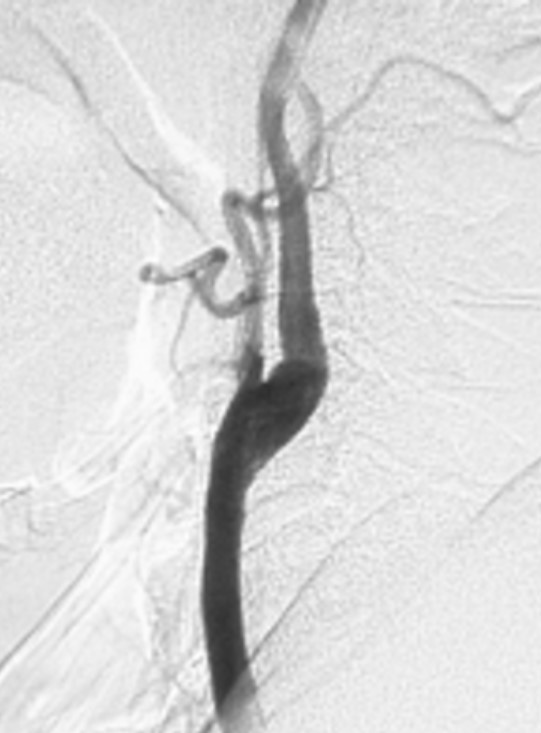

Figure 1: Preoperative DSA right common carotid arteriography lateral view of a 74-year-old man with cerebral infarction who developed moderate left hemiparesis and left homonymous hemianopsia. Severe stenosis of 71% was observed at the origin of the right internal carotid artery, and we considered that surgery for CEA was indicated. (NASCET method for calculating the stenosis rate = minimum diameter of blood vessel at stenotic part of internal carotid artery ÷ diameter of blood vessel at distal part of stenotic part) More than 100% vasodilation was obtained with CEA (Figure 2).

Figure 2